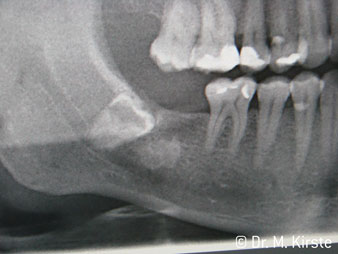

Le contre-angle avec tête angulée à 45° a surtout été choisi pour ses nombreux avantages. Les collègues qui exercent en chirurgie, et à qui cet instrument est principalement destiné, apprécieront très vite la possibilité de travailler efficacement dans des zones très étroites. En particulier, lors d’extractions de dent de sagesse (Ill. 2), où il n'y a pas besoin d’un grand angle d’écartement des tissus mous dans la région de la joue (Ill. 3). Pendant la préparation, une légère rotation de la tête de l’instrument permet un travail rapide et sans risque dans la zone rétromolaire.

Ill. 2